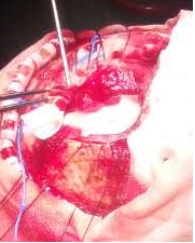

月11日上午9点30分,我院神经外科王冰主任亲自主刀,带领神经外科专业医疗团队,在麻醉科医师的协助下,为郭大爷行“额部肿瘤切除术+颅骨修补术”。术中发现病变组织竟然已侵蚀颅骨(图2),向头皮外生长,与脑组织及硬脑膜紧密粘连,侵犯矢状窦,手术过程中稍不留意就会出现大出血,风险极大。王冰主任凭借自己多年的临床经验及手术经验,临危不惧。经过近3个小时的不懈努力,终于完整清除郭大爷被肿瘤侵犯的脑组织、脑膜及颅骨(图3)。手术非常顺利。术后郭大爷神志清楚,恢复良好。现已转出神经外科监护室,到普通病区继续康复治疗。

图2 图3

(术中见肿瘤) (切除肿瘤后)